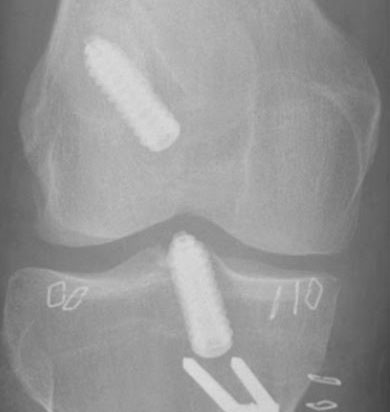

X-rays can detect loosening and osteolysis (bone erosion), as well as component wear, fracture, and malposition.

Wear and Loosening: Friction caused by the joint surfaces rubbing against each other wears away the surfaces of the implant, creating tiny particles that accumulate around the joint. In a process called aseptic (non-infected) loosening, the bond of the implant to the bone is destroyed by the body's attempt to digest the wear particles.

Fractures: The type and extent of the fracture will determine if revision surgery is needed. Fractures that disrupt the fixation or the stability of the implant may require revision surgery.

When a knee replacement fails, treatment depends on the cause of failure. Each case is unique and if there is more than the usual amount of bone loss extra pieces of metal or bone are added during revision knee replacement.